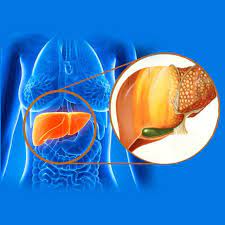

قیمت: 106٬000 تومان - دسته بندی فایل: پاورپوینتتظاهرات اختلالات کبدی

فروش ویژه پاورپوینت حرفه ای تظاهرات اختلالات کبدی با تخفیف استثنایی فقط 91 هزار تومان تعداد اسلاید: 57